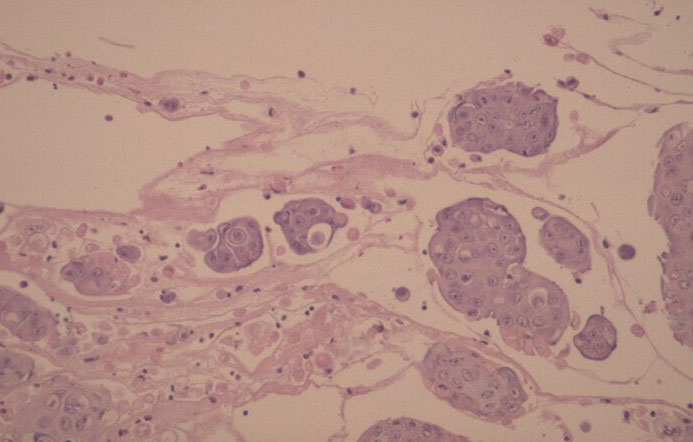

The earliest recognized change may be either eosinophilic spongiosis rarely or, more commonly, “spongiosis” in the lower epidermis . This spongiosis may actually represent the earliest manifestation of acantholysis rather than true spongiosis as defined earlier. Acantholysis leads first to the formation of clefts and then to blisters in a predominantly suprabasallocation . The intraepithelial acantholysis may extend into adnexal structures or occasionally be higher in the stratum spinosum. The basal keratinocytes, although separated from one another through the loss of attachment, remain firmly attached to the dermis like a “row of tombstones.” Within the blister cavity, the acantholytic keratinocytes, singularly or in clusters, have rounded condensed cytoplasm about an enlarged nucleus with peripherally palisaded chromatin and enlarged nucleoli. In some patients, there are varying quantities of antidesmoglein 1 and antidesmoglein 3 antibodies, leading to variable planes of acantholysis. There is little inflammation in the early phase of blister formation. If present, it is usually a sparse, lymphocytic perivascular infiltrate accompanied by dermal edema. However, if eosinophilic spongiosis is apparent, numerous eosinophils may infiltrate the dermis. The phenomenon of eosinophilic spongiosis occurs occasionally in other blistering diseases, particularly in their early phases, including acute contact dermatitis, pemphigus foliaceus, bullous pemphigoid, herpes gestation is, drug eruptions, spongiotic arthropod bite reactions, and transient acantholytic dermatosis. Several important changes ensue as the lesions age. First, a mixed inflammatory cell reaction consisting of neutrophils, lymphocytes, macrophages, and eosinophils may develop. Because of the instability of the blister roof, erosion and ulceration may occur. Older blisters may also have several layers of keratinocytes at the blister base because of keratinocyte migration and proliferation. Last, there may be considerable downward growth of epidermal strands, giving rise to so-called villi (Fig. 9-9D). The evaluation of patients with only oral lesions is difficult, because intact blisters are rarely encountered due to the trauma of mastication, and biopsies may show only erosion and ulceration. Indeed, it is best to sample the edge of a denuded area with intact mucosa in an attempt to demonstrate the typical pathologic changes. Clinicians frequently cannot distinguish between an ulcer and the intact mucosa, as both are often white and shaggy. In patients with only oral lesions, biopsies of intact oral mucosa for DIF testing are more sensitive than biopsies of lesions for routine light microscopic evaluation. Therefore, biopsy from the normal maxillary and upper buccal mucosa is necessary when there is extensive ulceration. Cytologic examination using a Tzanck preparation is useful for the rapid demonstration of acantholytic epidermal keratinocytes in the blisters of pemphigus vulgaris. For this